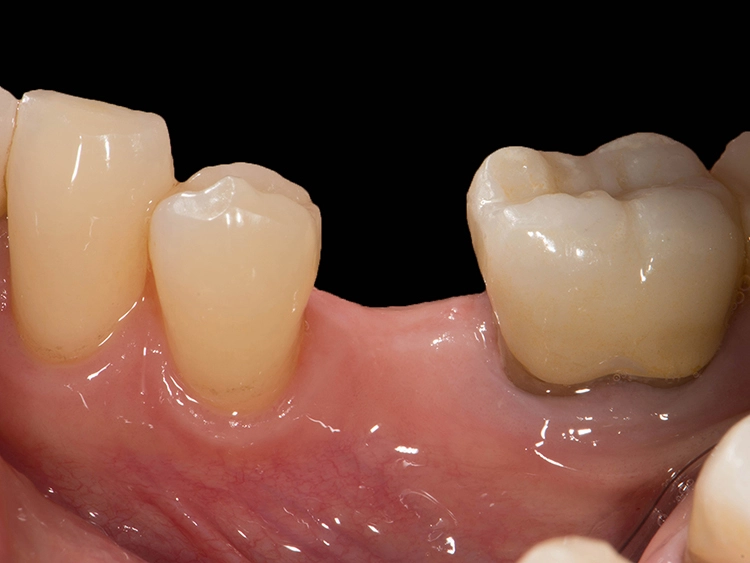

Zweiteilige Implantatsysteme würden darüber hinaus mit einer höheren prothetischen Flexibilität punkten, weil die Aufbauten individueller gestaltet werden können. Dr. Röhling: „Das kann ein Vorteil sein, wenn etwa die prothetische Achse korrigiert werden muss.“ Hinzu kommt, dass bei Anwendung von zweiteiligen Systemen eine Zementierung, die für Fehlerquelle anfällig gesehen wird, entfällt, da sie eine reversibel verschraubte Befestigung erlauben, während bei einteiligen Implantaten die Suprakonstruktion nur zementiert gestaltet werden kann (siehe Fallbeispiel, Abbildungen 1 bis 10).